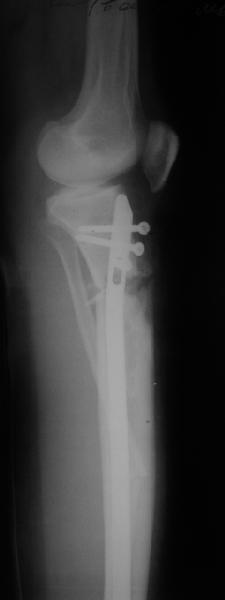

Продолжение обсуждения, начатого в октябре прошлого года (см. здесь) Наконец-то оперировали эту пациентку. Биопсию сделали - опухолевого ничего нет. Пока все участвовавшие в обследовании смежные специалисты и ортопеды сошлись, что это молокальная монооссальная фиброзная дисплазия. 20 марта наложили аппарат, сделали чрескожную остеотомию. К 3 апреля все докрутили. Сегодня заштифтовали. Начальные и итоговые снимки в приложении. Рекурвацию можно было еще немного больше устранить, и чуть кзади сместить диафиз. Но вроде и так ничего выглядит, по сравнению с тем, что было. Комментарии приветствуются.

Александр, по моему великолепно. Поздравлять будем, когда продемонстрируете консолидацию,функцию и внешний вид.

Вопрос: почему дистально только один винт? Предполагаете ли динамизацию?

АС> Вопрос: почему дистально только один винт?

Второй тут можно было сделать динамический, но отломок очень уж длинный, и ротационной подвижности даже без винтов не будет.

АС> Предполагаете ли динамизацию?

Если не успеет срастись месяца за два, то этот винт и уберем.

vsХ> и достаточна ли на Ваш взгляд будет межотломковая

vsХ> компресия,учитывая короткий рычаг,проксимального фрагмента и

Есть клиновидный диастаз, контакт основных отломков на очень небольшой площади только в задненаружном отделе. Так что там скорее межотломковая дистракция, а не компрессия.